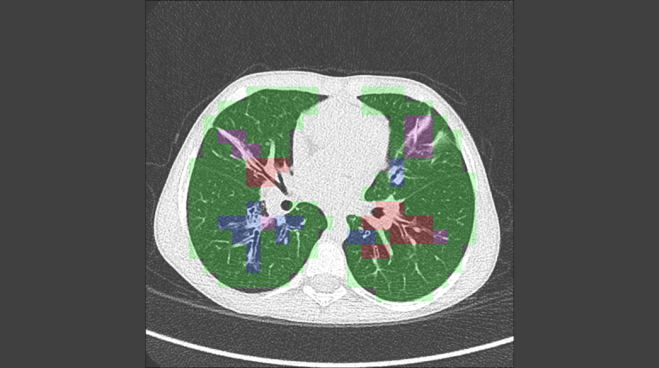

The patent allows Thirona to develop an AI algorithm that will analyse CT scans to identify even the smallest abnormalities in the lungs, especially early on, ensuring that the right treatment can follow.